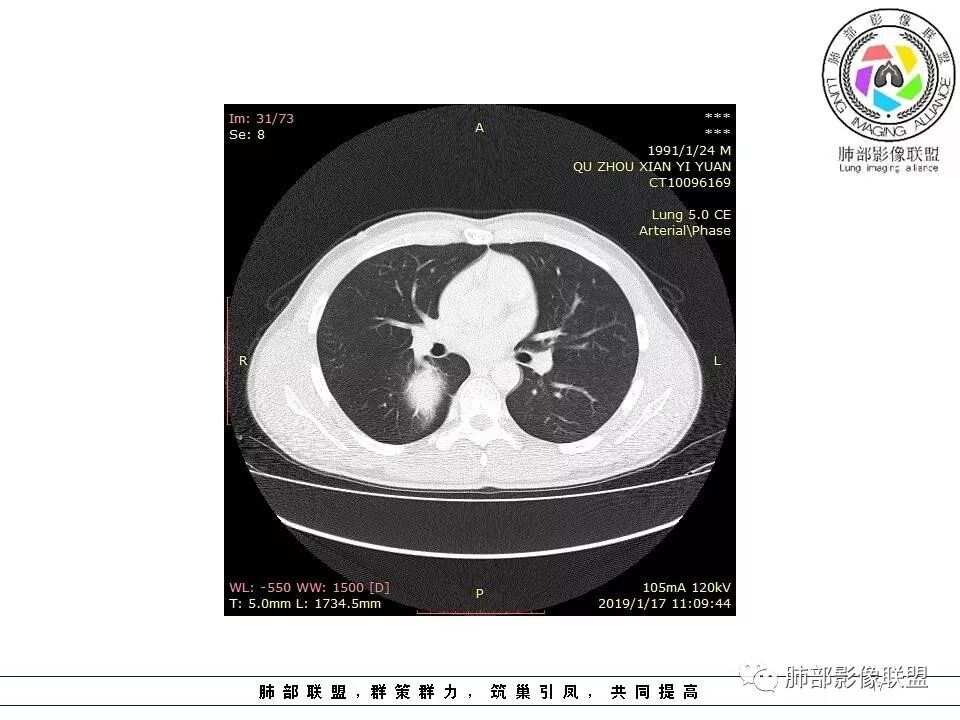

右后纵膈脊柱旁软组织占位,形态规则类圆,边缘光整,肺组织受压,胸膜尾,肋间动脉供血。中度不均匀延迟强化。

后纵隔脊柱旁占位性病变,疾病谱有神经鞘瘤,sft,节细胞瘤,髓外造血。此例有胸膜尾征,蛇纹征 ,延迟强化。考虑胸膜孤立性纤维瘤。看到有供血动脉,但不知道是哪里的血管。

后纵隔类圆形新生物,边缘光滑,胸膜尾征明显,贴近脊柱,蛇纹,血供丰富,考虑后纵隔软组织肿瘤,具体类型看不出来,鉴别神经鞘瘤。

右后纵膈脊柱旁软组织占位,边界清晰,光整,肺组织受压。胸膜被掀起,肋间动脉供血,中度不均匀延迟强化。考虑神经鞘瘤,不除外纤维瘤

右后纵膈脊柱旁软组织影,与纵隔结构分界不清,形态规则类圆,边缘光整,肺组织受压,胸膜尾,肋间动脉供血。肺动脉推移,中度不均匀延迟强化。考虑神经来源,神经鞘瘤,神经纤维瘤二者不易鉴别。

青年男性,间断胸痛;右侧脊柱旁可见一类圆形软组织密度影,密度欠均匀,增强扫描呈轻中度持续强化,邻近肺组织及肺动脉推移,可见肋间动脉供血,部分胸膜下脂肪可见,部分层面似见与右侧椎间孔相连。考虑后纵隔神经源性肿瘤。

1.右上胸内脊柱旁类圆形肿块,质地似乎比较坚实,密度稍显不均,但未显示明确的坏死。

如此密度形态的病灶位于肺边缘首先应当想到孤立性纤维瘤,可相邻胸膜未见明显的异常强化和胸膜方向延伸。

注意所谓“胸膜尾征”的概念及形成机制与“脑膜尾征”是大不相同的。